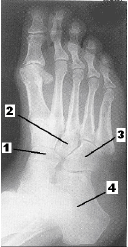

Após analisar atentamente a figura abaixo, responda à questão.

A imagem acima corresponde a uma incidência em